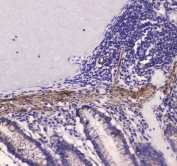

IHC testing of FFPE mouse small intestine tissue with MYLK antibody at 1ug/ml. Required HIER: steam section in pH6 citrate buffer for 20 min and allow to cool prior to staining.

IHC testing of FFPE rat small intestine tissue with MYLK antibody at 1ug/ml. Required HIER: steam section in pH6 citrate buffer for 20 min and allow to cool prior to staining.